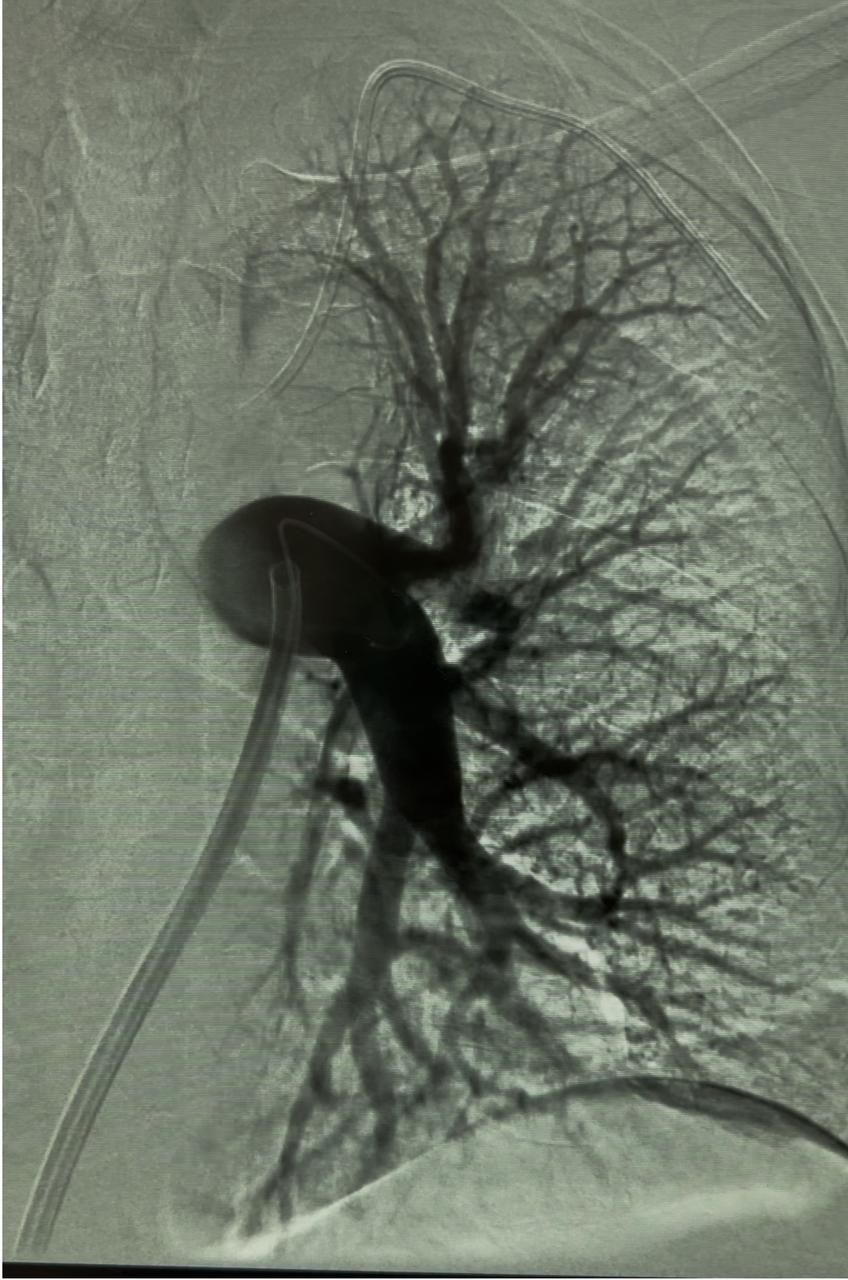

Usually, access was gained in the right femoral vein, and a 16-F, 65-cm Gore DrySeal sheath (Gore & Associates) was introduced into the vasculature and placed in the right or left main pulmonary artery (PA). A Lightning Flash HTORQ was then advanced into the right main PA. To place Lightning Flash into the correct anatomy, the catheter was deftly tracked over a 6-F Select Catheter (Penumbra, Inc.) with a Bernstein tip shape and a 0.035-inch Amplatz guidewire (Boston Scientific Corporation). With the catheter in place, aspiration was initiated. In 2.5 minutes of device time, the thrombus burden was extracted from the right or left main PA (Figure 1),

Figure 1: Thrombus burden was extracted from the left main pulmonary artery

and pulmonary angiography displayed considerable improvement from the beginning of the case (Figure 2).